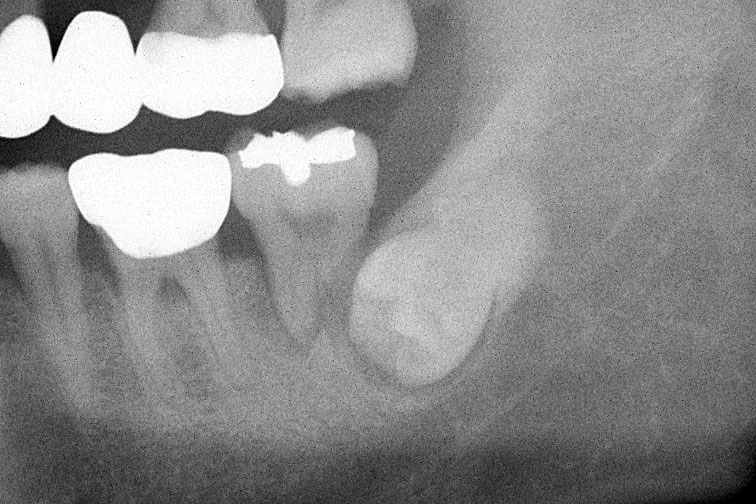

사랑니 발치

사랑니 발치는 분명히 힘들고 어려운 치료입니다.잇몸을 절개하고 치조골을 삭제하는 방법, 치아를 절단하는 과정에서 노하우가 필요합니다. 또한 신경손상등의 합병증을 최소화하기 위해 경험 많은 의료진의 진료가 필요합니다.

• 예전에는 치과용 CT 촬영이 보험 적용이 어려워 부담스러운 진단 장비였습니다. 지금은 하치조 신경 손상 가능성이 높은 사랑니 발치의 경우에는 보험 적용이 되어 저렴하게 정확한 진단이 가능하게 되었습니다.

• 내인생치과에서는 CT를 사용하여 사랑니와 하치조 신경의 관계를 분석하여 수술에 도움을 주고 있습니다,

• 구강악안면외과 전문의이자 현 서울삼성병원 외래교수인 대표원장의 10년이 넘는 임상경험을 바탕으로 대학병원 수준의 치료를 보장합니다.